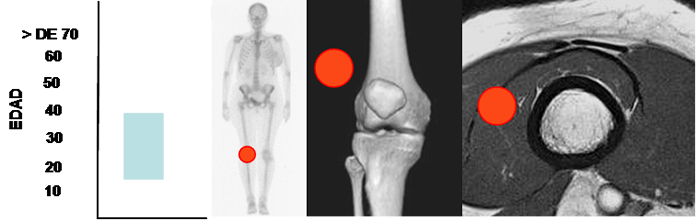

Ocurre en adolescentes y adultos jóvenes, entre los 15 y 40 años, con predominio en la fosa poplítea. (50, 51). (Fig 199).

Mayor frecuencia entre 15 y 40 años. Lesión de tejidos blandos, con predominio en la fosa poplítea.